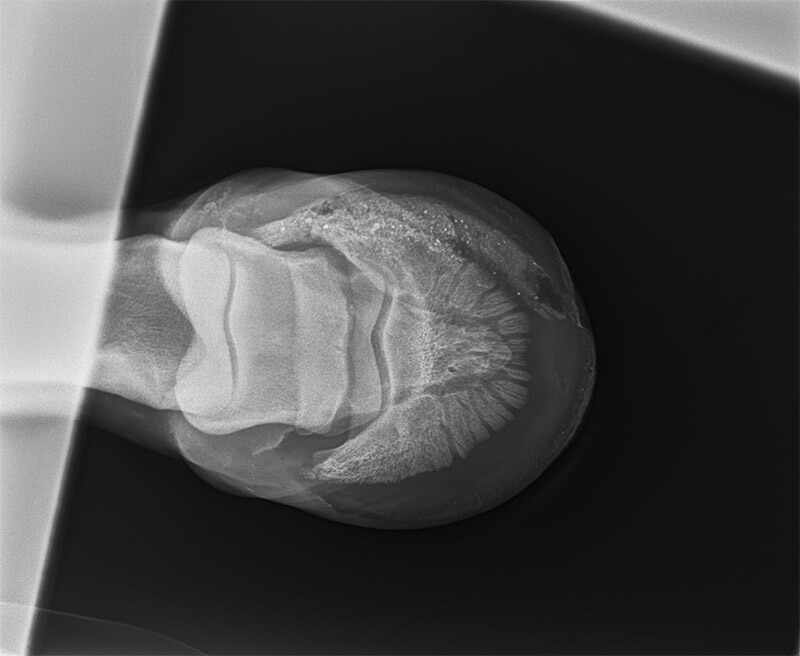

This is a foot abscess that wouldn’t heal; see subsequent X-rays below.

A – An underrun sole; this is the X-ray showing debris inside the hoof. B – This is an X-ray after the muck was syringed out of the hoof. The large black hole is the clean cavity.

“The underrun sole occurs when

insufficient drainage occurs and the abscess

spreads along under the sole.”

The sole was opened to clean out the muck and the horse was much improved after.

In these cases, a large cavity exists between the old sole and what has become the newly keratinised sole (so the pedal bone is not exposed). Pus and sometimes debris are caught between what are effectively two soles, causing an ongoing lameness. The farrier will sometimes pick this up when examining the foot, knowing that multiple break outs have occurred, and the abscess has been “going” for several weeks. On other occasions the vet may diagnose an underrun sole after X-rays are taken due to the chronic nature of the lameness. Once the dead sole is pared back and the pus or debris removed, the lameness usually resolves quickly and the horse can return to work, although it may require some packing of the foot with iodine swabs or some form of sole packing, until the new sole is fully formed and hard enough to resume normal wear.